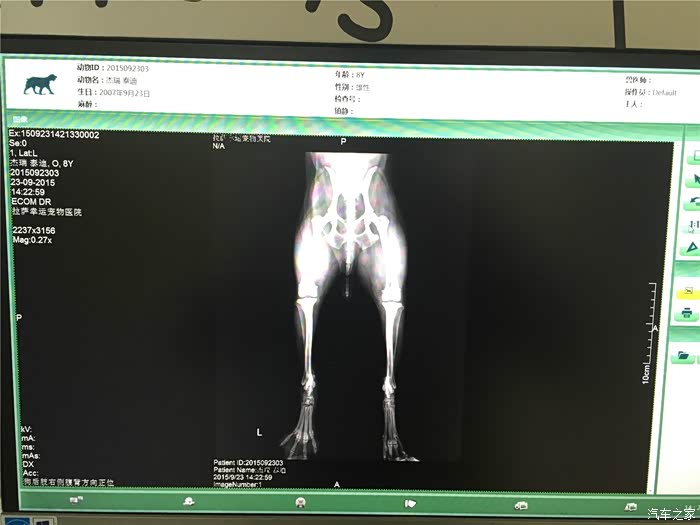

回拉萨途中,dido妈已经告诉我,他们找到了一家宠物医院,是拉萨警犬指定医院,有dr设备,据说比X光更好

上海的医生朋友也说,dr设备还是比较先进的,看的比较清楚

拍片。果然是骨折了,但是并不算严重,骨头甚至没有完全断开。

医生建议外部固定,静养恢复。

询问了上海的宠物医生,把dr图拍下给他看过,也说可以外部固定。